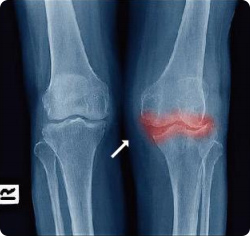

注:x线图像显示左侧正常老年膝关节与右侧骨关节炎膝关节的对比。

正常关节,关节间清晰可见

膝关节炎,关节间隙消失